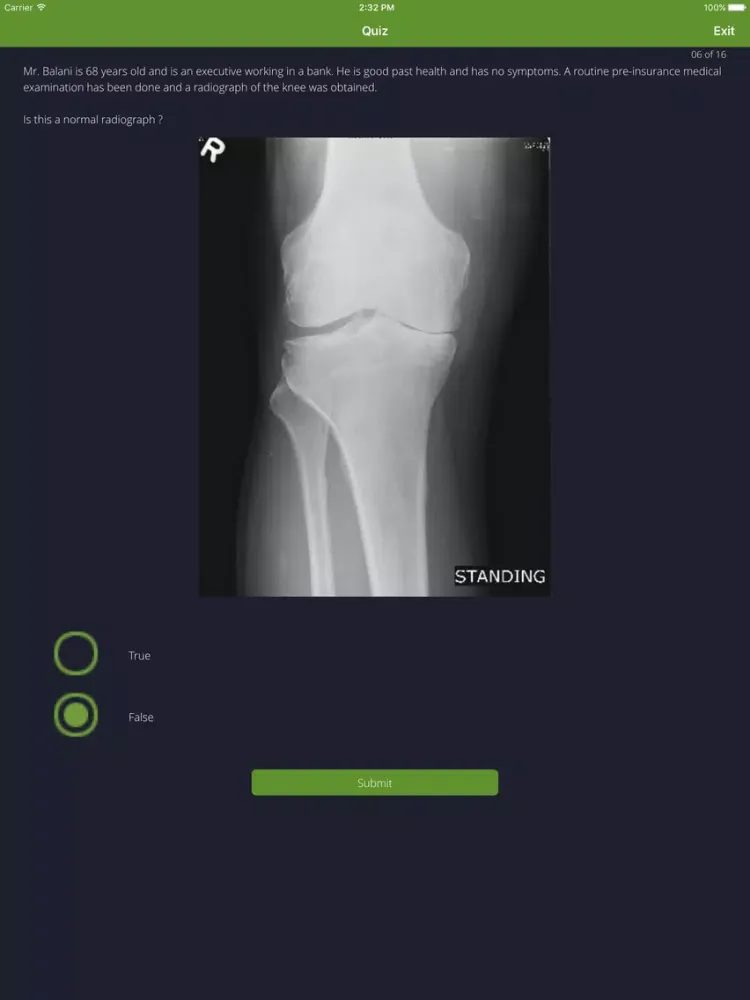

- A quiz designed to test your knowledge of musculoskeletal medicine and introduce you to basic film interpretation skills. A 'hint' dialogue box appears after submitting an answer, encouraging you to re-evaluate your interpretation.

- Review clinical situations on the basis of case examples in a format similar to that of clinical vignettes.